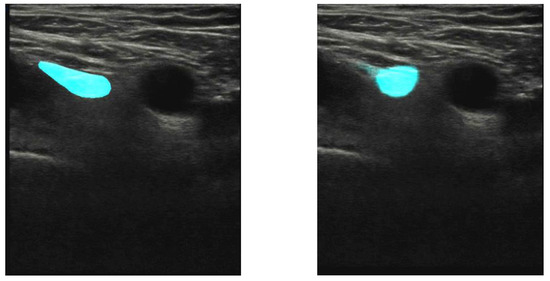

Figure 4.

Test image of a participant’s right groin, the same as used in Figure 1. The femoral artery is seen as a black circular area in the center of the image. Left panel: expert’s manual annotation of the femoral nerve (cyan). Right panel: trained U-net segmentation of the femoral nerve. The overlap between the annotated and segmented areas, described as IoU, is 57% in this case.